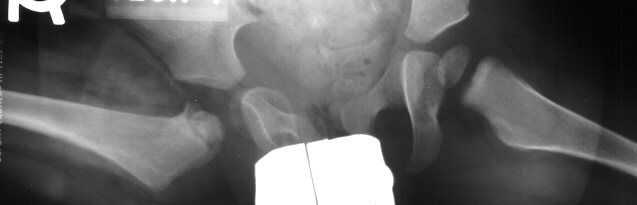

This case is an example of untreated septic arthritis which caused avascular

necrosis of the proximal femur. The primary cause of this is undrained

septic hip. Repeated aspiration is not adequect treatment of a septic hip.